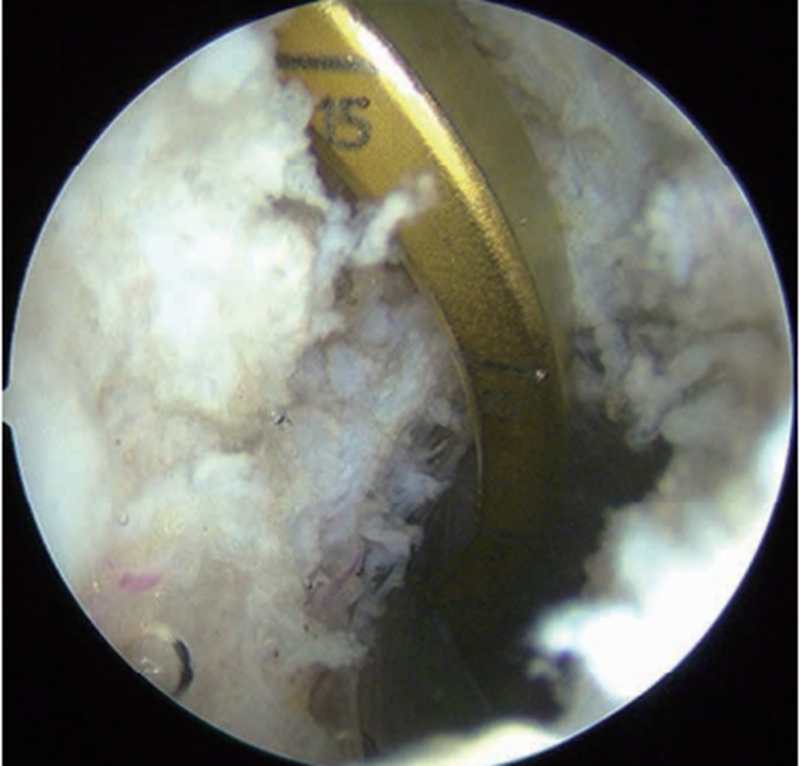

3.制备胫骨隧道

做膝关节后内与后外侧入路(图5),适当清理PCL残端周围滑膜、脂肪和后纵隔,显露PCL胫骨止点及其下方至少20mm深度的胫骨后缘(图6)。胫骨定位器从髌内侧入路置入,跨过ACL上方从PCL残端内侧绕至胫骨后方斜坡下定位。为避免“杀手转角”(killer turn)(图7),胫骨定位器前端应尽量伸至胫骨平台下方20mm或更低处(图8),跨过PCL在原斜坡上的止点,以确保移植物出胫骨隧道内口后附着处为隧道钝角,减少韧带磨损切割(图9)。

图5 膝关节后内侧入路建立方法

从膝关节后外侧入路经后外侧间室,穿过后纵隔到后内侧间室,光源照射直视下做后内侧入路

图6 PCL胫骨残端后方情况

适当清理PCL残端周围滑膜、脂肪和后纵隔,显露PCL胫骨止点及其下方至少20mm深度